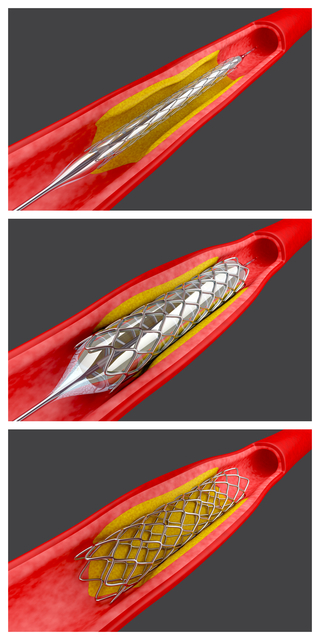

心臓用カテーテルをはじめ、

- 血管カテーテル等循環器部門の販売に進出。

- 米国のバイオメディカル社と独占販売代理店契約(血管バルーンカテーテル)

- アンジオメディックス社と独占販売代理店契約(ソフチップ・血管カテーテル)

- スイスのシュナイダーシャイリー社と独占販売代理店契約(血管カテーテル)